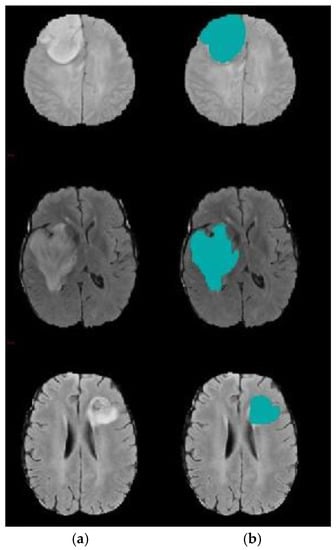

3.3. Level Set Segmentation

| 1: Insert initial contour points using two-step DA clustering output (ROI indexes). 2: Construct a signed distance function. 3: Calculate feature image using Gaussian filter and gradient. 4: Obtain the curve’s narrow band. 5: Obtain curvature and use gradient descent to minimize energy. 6: Evolve the curve. 7: Repeat step number two and stop after obtaining the segmented region. |